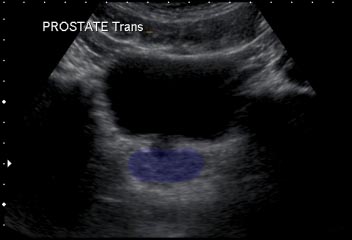

Transabdominal

In a transabdominal examination, the bladder is situated above the prostate

Transverse